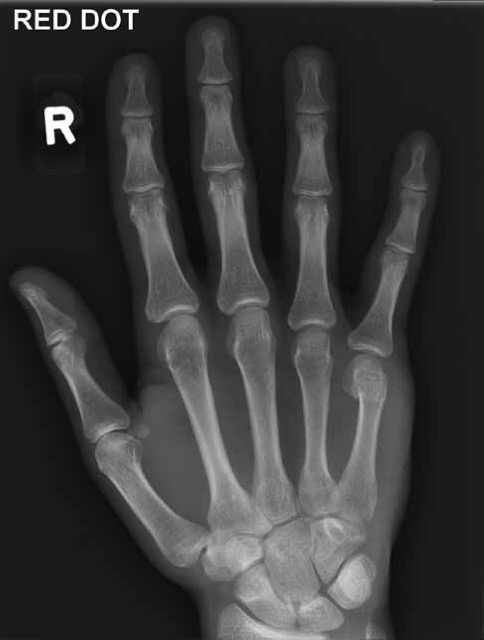

Orthopaedic

4 pattern guides